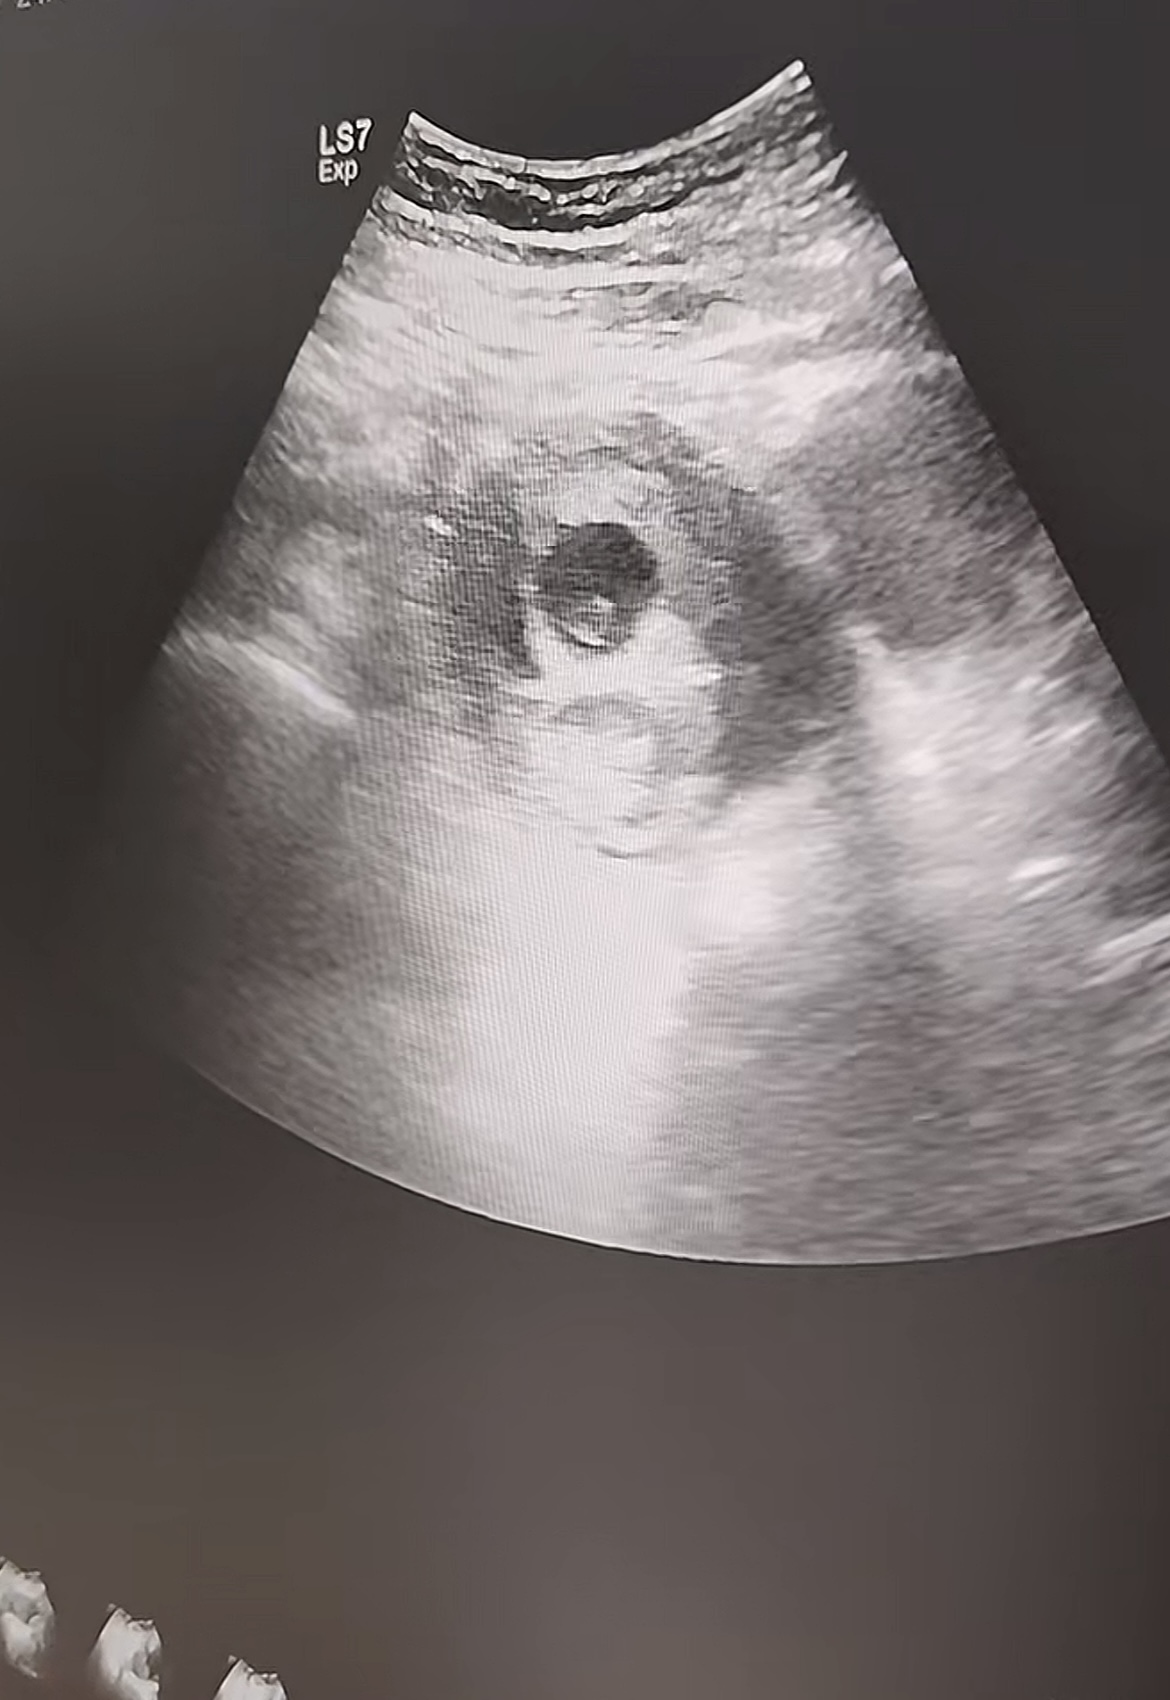

我们的核心优势在于 “可视” 。手术在高清超声影像引导下进行,医生可以清晰看到宫腔内孕囊的准确位置与大小。手术器械能精准定位、吸附,只对目标组织进行吸取,有效避免了对正常子宫内膜的过度刮拭,极大降低了子宫损伤和穿孔的风险。